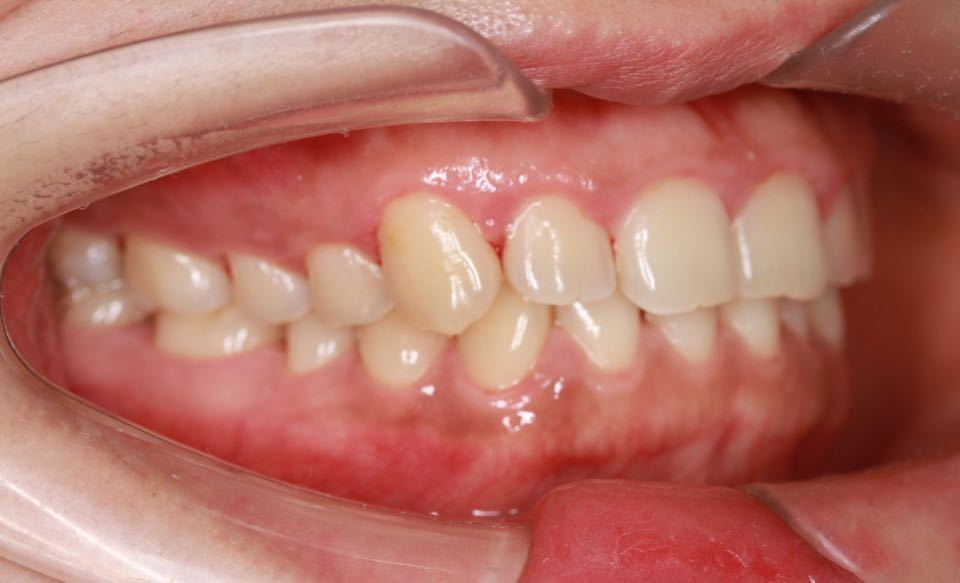

矫正前口内照:

口内:恒牙列,牙列拥挤(中度)。上下颌牙弓呈方圆型。左右对称。右侧磨牙近中性关系,左侧磨牙近中关系,右侧尖牙远中关系,左侧尖牙远牙中性关系。上颌中线偏右2mm,下中性居中。